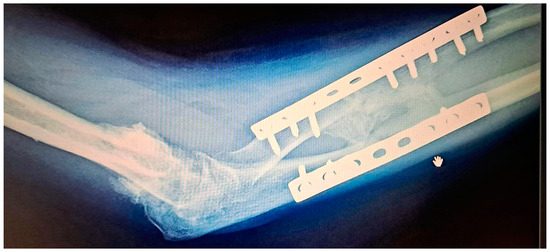

Surgical Treatment of Post-Traumatic Radio-Ulnar Synostosis

Radio-ulnar synostosis is a rare complication which develops following forearm trauma, the main manifestation being stiffness and leading to the loss of pronation and supination. For the patient, it is a very frustrating experience due to the impairment of the normal function of [...] Read more.

Radio-ulnar synostosis is a rare complication which develops following forearm trauma, the main manifestation being stiffness and leading to the loss of pronation and supination. For the patient, it is a very frustrating experience due to the impairment of the normal function of the forearm, whereas for the surgeon the treatment is difficult as, unfortunately, there is no consensus regarding the best way to approach it. Many surgical techniques and other kinds of adjuvant therapies have been developed in an effort to solve this disability. This paper presents an overview of the principal factors which contribute to the development of synostosis and the best therapeutic approach methods found in the literature. Full article